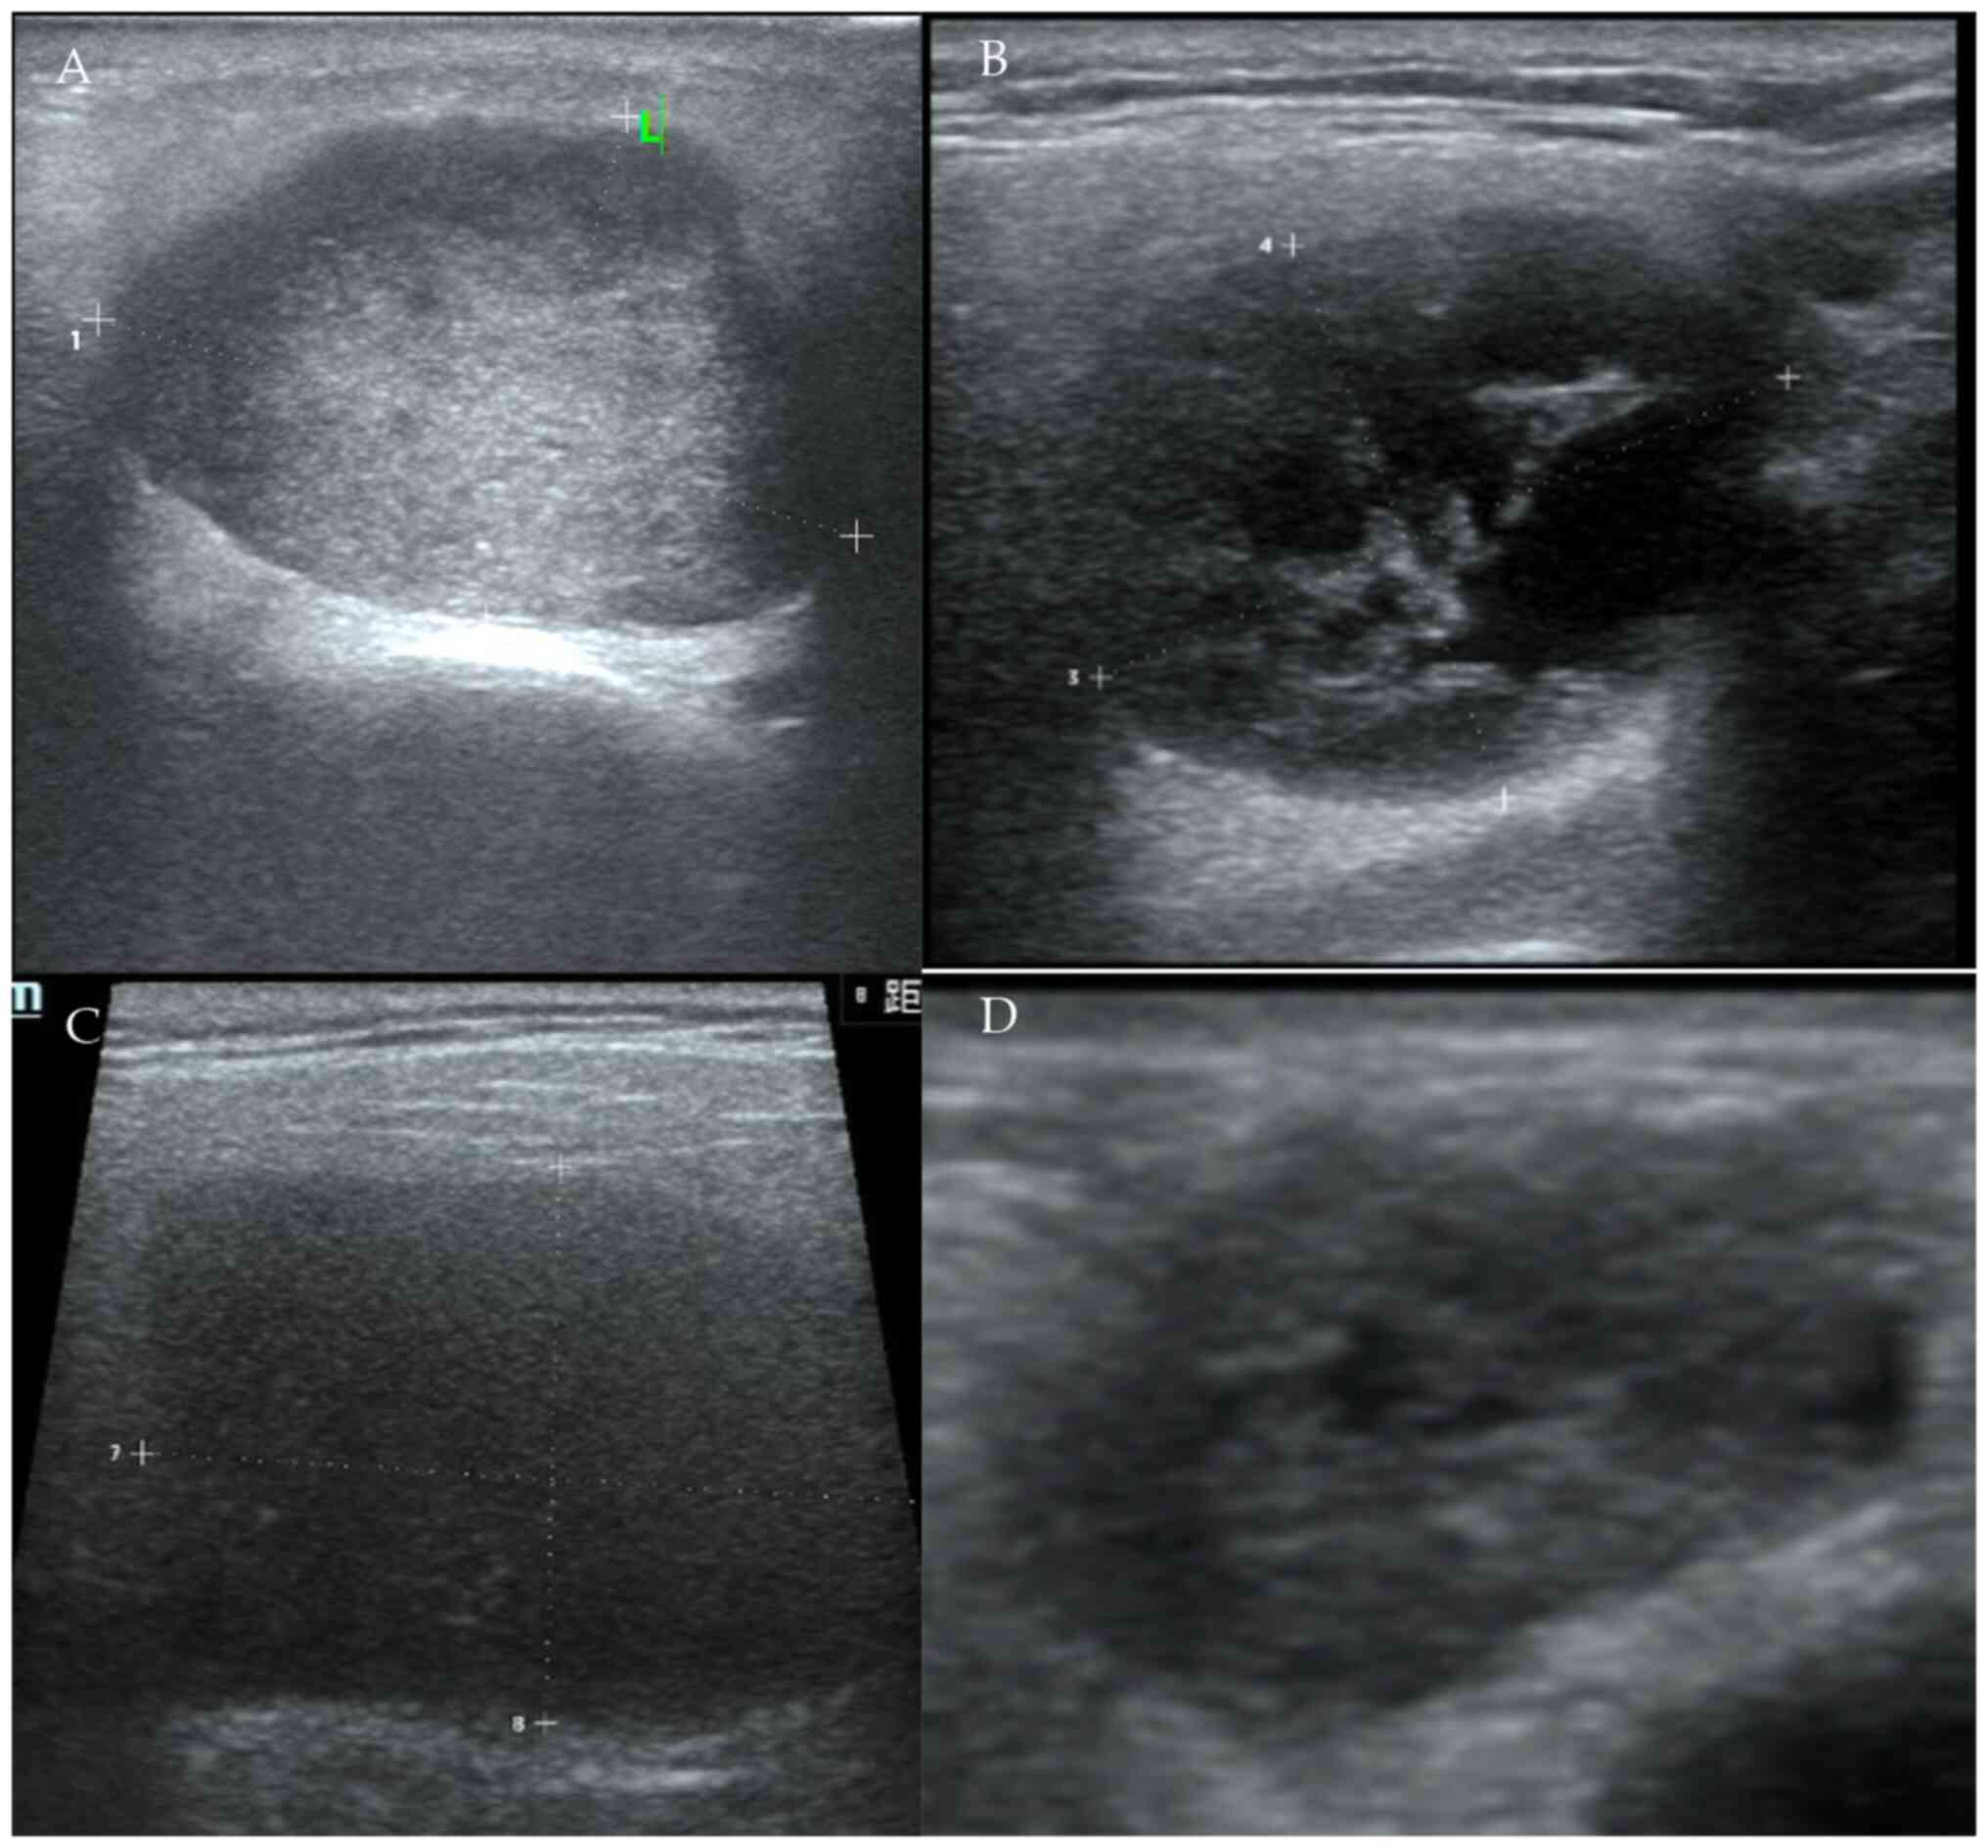

By contrast, US examination was performed by an US technologist with >5 years of experience in ultrasonography of the head and neck regions with Mindray DC-80 (Mindray Medical International Co., Ltd.). US assessment showed a series of characteristics, such as the tumor's size, shape (regular or irregular), homogeneity (mildly or highly heterogeneous), echogenicity (slightly hypoechoic or highly hypoechoic) and vascular pattern within the tumor (avascular or reduced vascularity, moderately vascularized or highly vascularized) (Fig. 1). A regular shape, well-defined margins, homogeneous echogenicity, a weak vascular pattern and the absence of enlarged intraparotid or cervical region lymph nodes were considered predictors of a benign tumor. However, an irregular shape, poorly defined margins and heterogeneous echogenicity were considered predictors of a malignant tumor (Fig. 2) (10,24).

Echogenicity and heterogeneity of

parotid gland tumors under ultrasound. (A) Slightly hypoechogenic

and slightly heterogenic pleomorphic adenoma. (B) Highly

hypoechogenic and highly heterogenic WT. (C) Highly hypoechogenic

and slightly heterogenic WT (D) Slightly hypoechogenic and highly

heterogenic mucoepidermoid carcinoma. WT, Warthin's tumor.

Figure 1

Echogenicity and heterogeneity of parotid gland tumors under ultrasound. (A) Slightly hypoechogenic and slightly heterogenic pleomorphic adenoma. (B) Highly hypoechogenic and highly heterogenic WT. (C) Highly hypoechogenic and slightly heterogenic WT (D) Slightly hypoechogenic and highly heterogenic mucoepidermoid carcinoma. WT, Warthin's tumor.